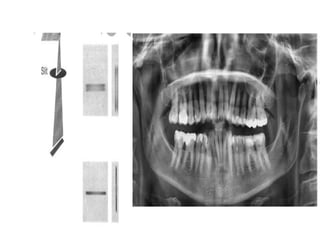

• 17.

Pan Tomography ‱ Itis a tomography method used still today is dental radiographic procedures that produce a panromaic image of a curved surface. ‱ The patient is kept stationary during the procedure. ‱ Film is exposed here through a narrow slit in its holder and moves it as tube rotates and image is laid out as film passes through the slit.